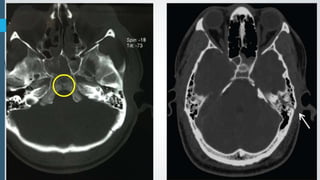

Diffuse axonal injury. CT scan demonstrates small hemorrhagic diffuse axonal injuries

in the deep white matter and corpus callosum.

Multiple hemorrhagic foci post MVA, involving the left thalamus and corpus callosum's splenium,

compatible with DAI.